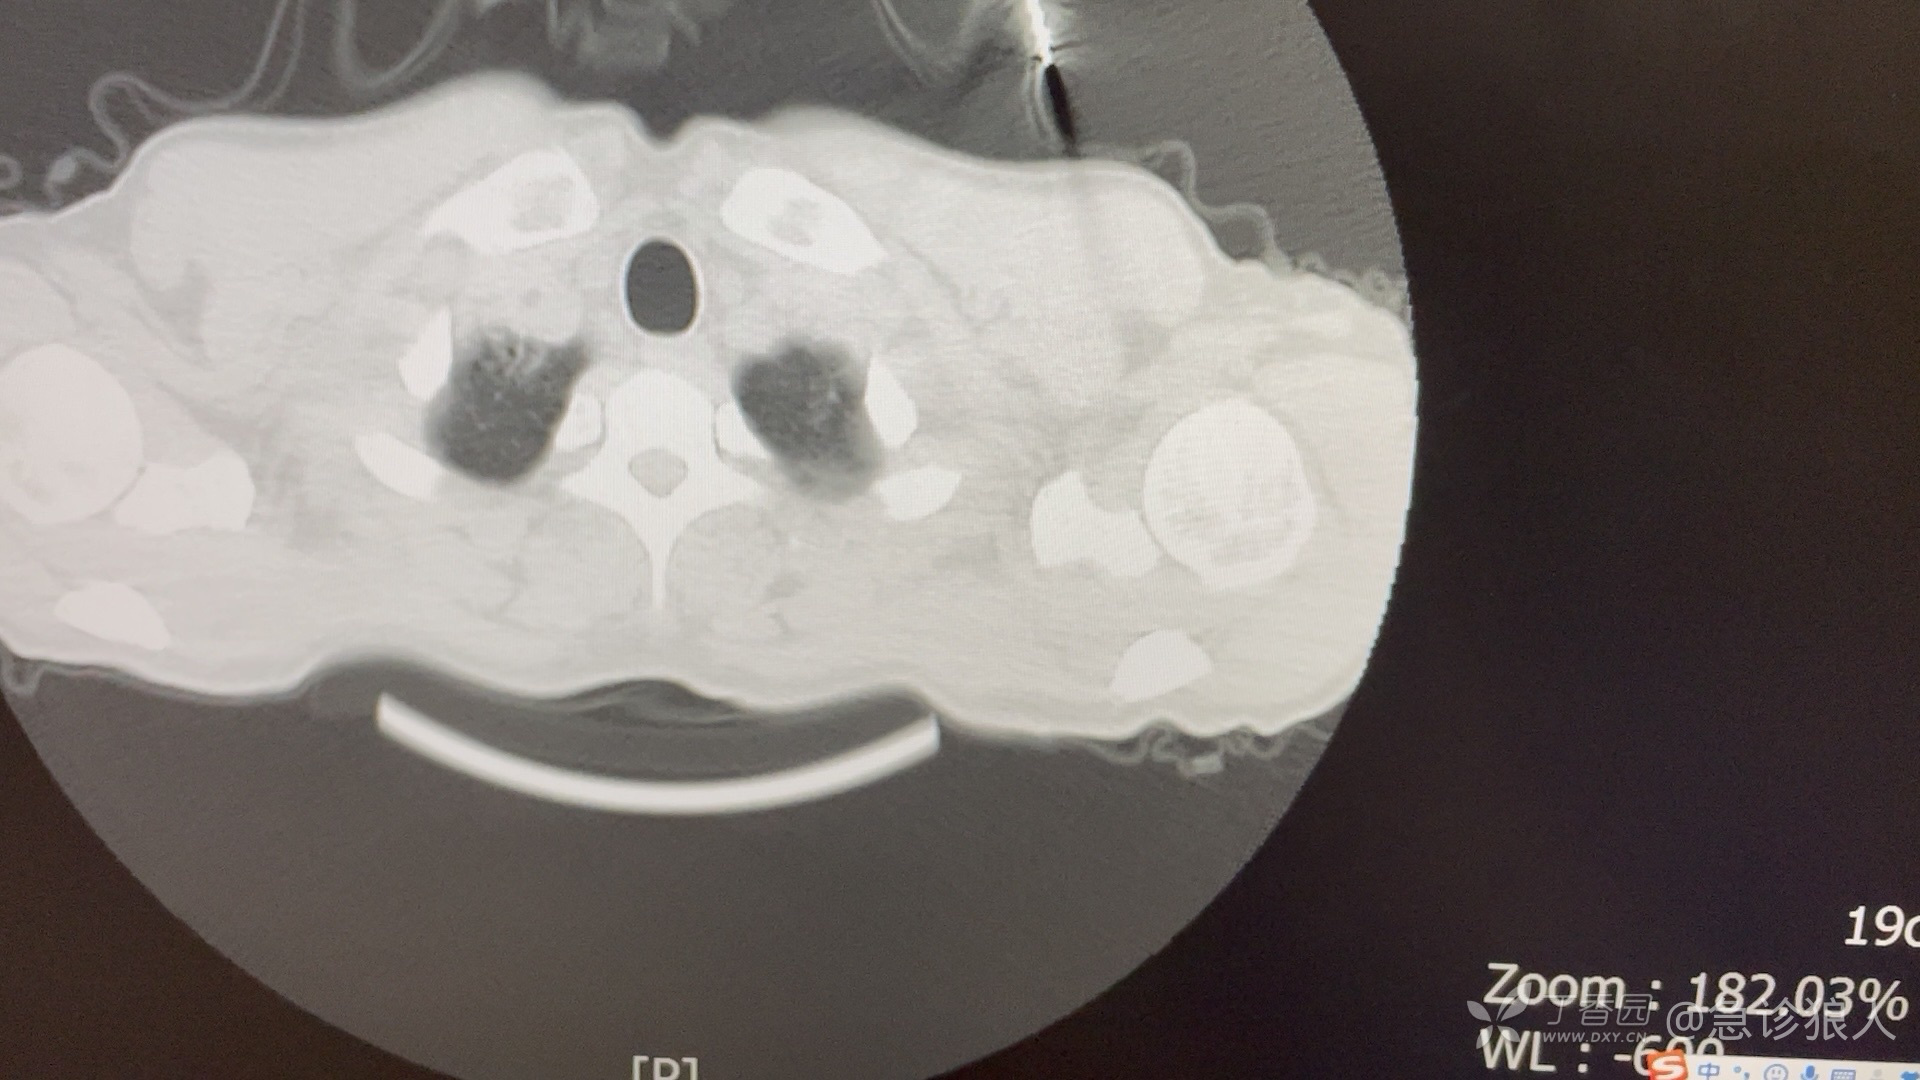

肺泡蛋白沉积症(pulmonary alveolar proteinosis, PAP)又叫肺泡磷脂蛋白沉积症,是一种弥散性肺部疾病,特征是远端气腔有过碘酸-希夫染色(periodic acid-Schiff, PAS)阳性的无定形脂蛋白样物质蓄积。患者几乎没有肺部炎症,并且基础肺结构正常。该脂蛋白样物质主要由表面活性物质磷脂和载脂蛋白组成。